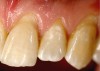

As dentistry continues to embrace minimal intervention restorative approaches, materials that are truly restorative and therapeutic, versus inert, will be required. Direct composites have recently been introduced that are bioresponsive and demonstrate bioactivity in terms of fluoride release, inhibiting marginal demineralization after acid exposure, and decreasing the biofilm that accumulates subgingivally and contributes to plaque.15-17 Such characteristics are essential when creating artificial gingiva and restoring pink esthetics for patients who present with gingival recession (Figure 2), because biofilm and plaque development could result in inflammation of the surrounding natural tissues, caries, and future esthetic compromises.

Fig 2. Preoperative view showing the absence of pink on teeth Nos. 9 and 11.

Figure 2